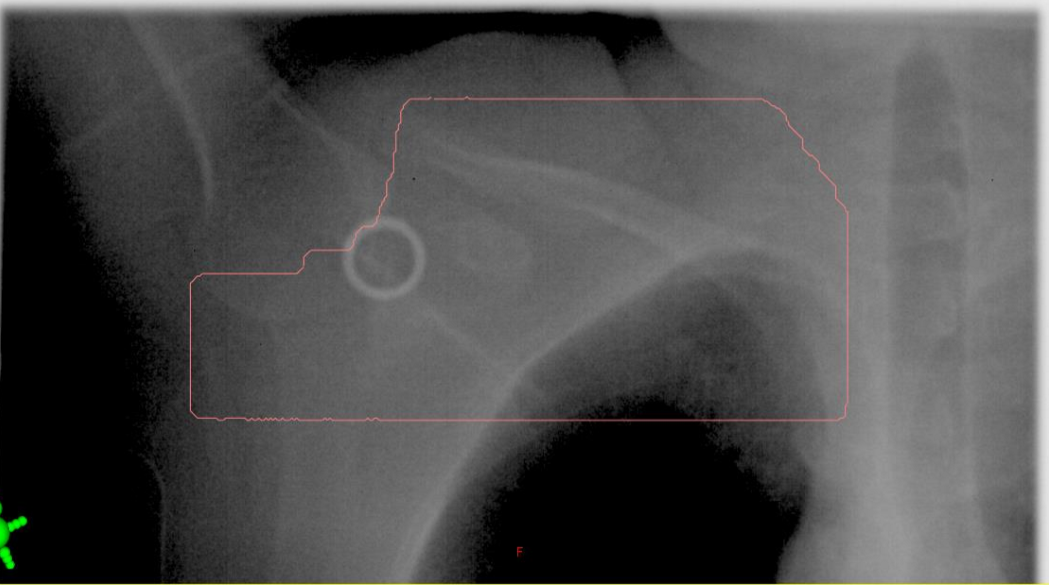

BEV - treatment field images

typically MV image quality

at what angle and MLC set-up are BEVs taken at?

taken at the treatment angle wit the MLC in place

important: what 4 things are we evaluating with the BEV image assessment

MLC shielding (in relation to the patient)

lung volume

treatment field clearance (sup, inf and ant) around the breast

bolus if applicable

BEVs are not used for field localization, but they are used to verify / confirm …

verify and confirm position of the treatment beam

what imager is used to take the BEV image

MV EPID imager

this is done to ensure field borders and MLC are within the image

what are the MLCs the arrow is pointing to shielding?

we are shielding the thyroid

what two lymphatic nodes are being included in the BEV?

we are shielding the acromioclavicular joint

two nodes: supraclavicular and axillary nodes

on a supraclav BEV, what three thing are we assessing?

arm position (see clavicle and humoral head)

field borders relative to patient anatomy (sup, inf, medial, lateral)

MLCs relative to the patient’s anatomy

when looking at a supraclav BEV, do we assess lung volume?

NO, it is irrelevant on this field, just assess the field borders